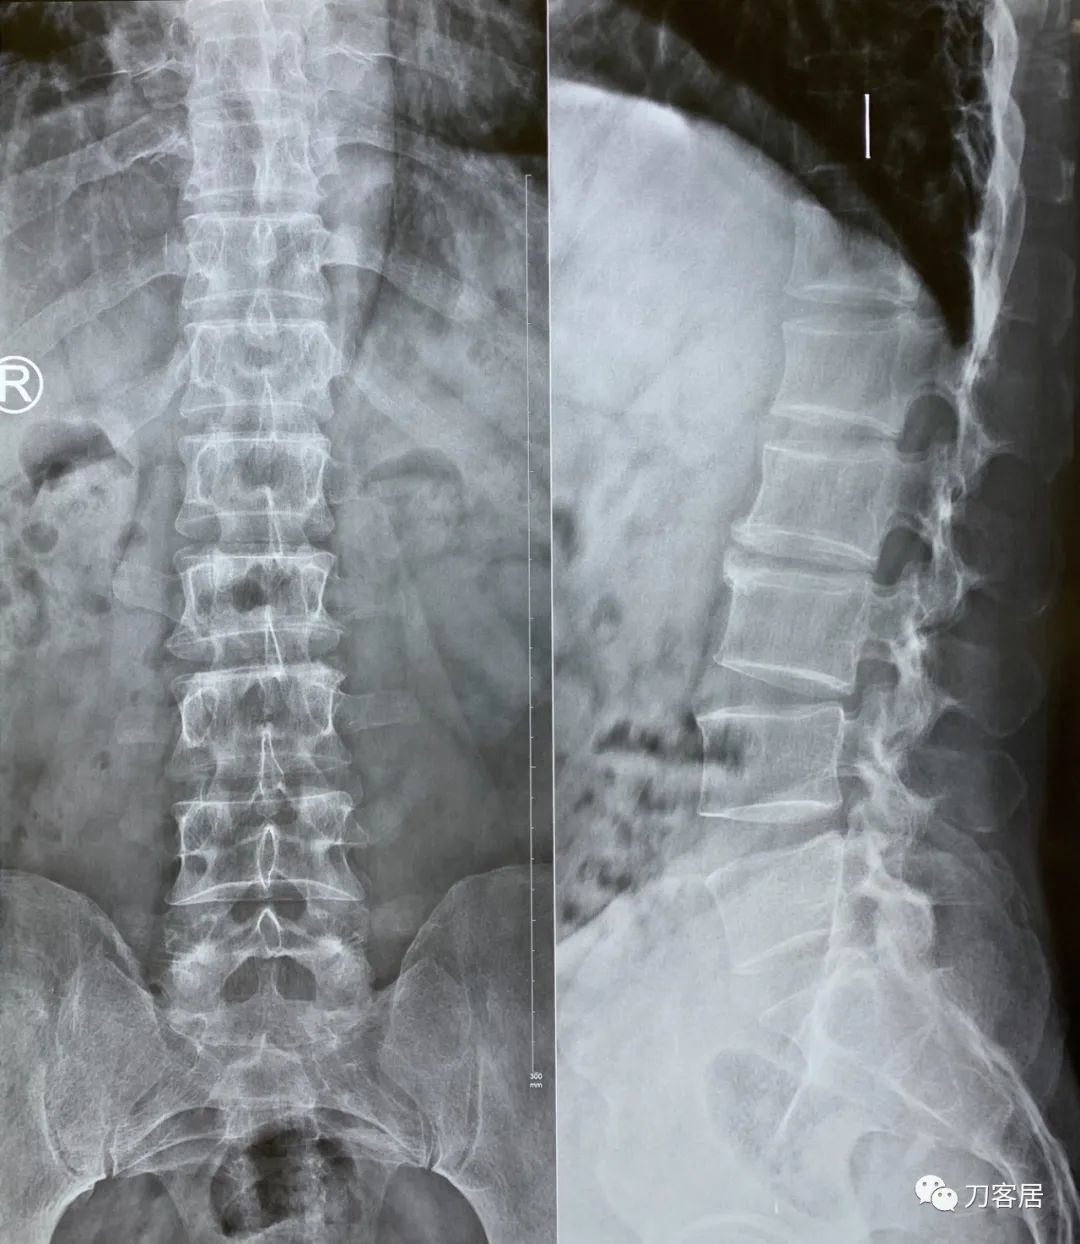

2023年1月30西京医院腰椎正侧位X线片,提示骨质疏松,腰2椎体压缩骨折,不严重。

虽然该患者携带的磁共振片子上显示腰2椎体压缩骨折是新鲜骨折,但该片子是2021年9月1日的片子,已过1年5个月,骨折已是陈旧骨折,拍摄普通X线片证明腰2椎体压缩骨折较前无加重,因此无需再做腰椎MRI片子,节省患者的费用。